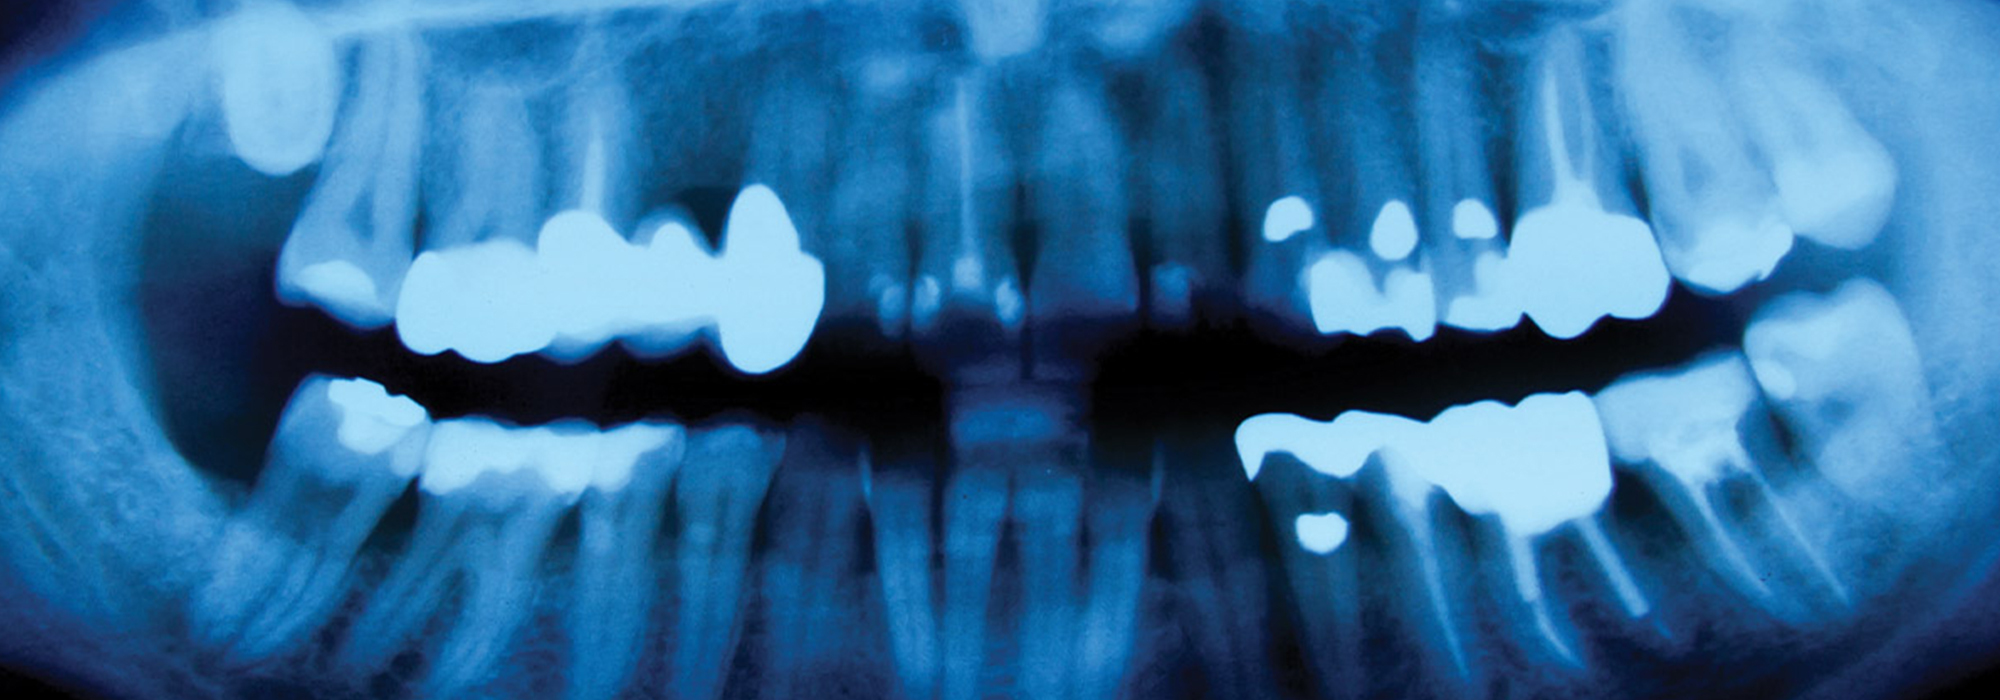

- Emergency Exam: The patient will be examined by a dentist to determine the extent and severity of the injury. The dentist will take x-rays to see the damage inside the tooth or jaw, and determine the best course of treatment.

Dental traumatic injuries refer to any damage to the teeth or supporting structures (such as the gums, jawbone, or ligaments) that results from an external force. These types of injuries can range from minor to severe and can affect one or multiple teeth.